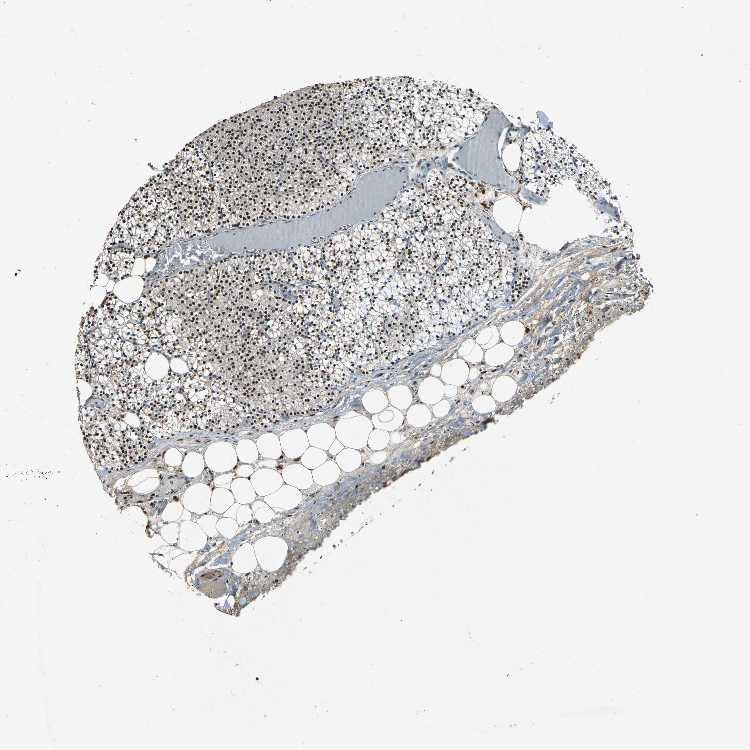

TISSUE PRIMARY DATA PARATHYROID GLAND Show tissue menu

Parathyroid gland

PARATHYROID GLAND - Expression summary

PARATHYROID GLAND - Antibody stainingi

Antibody staining in the annotated cell types in the current human tissue is reported as not detected, low, medium, or high, based on conventional immunohistochemistry profiling in selected tissues. This score is based on the combination of the staining intensity and fraction of stained cells.

Each image is clickable and will lead to virtual microscopy that enables deeper exploration of all samples and also displays staining intensity scores, fraction scores and subcellular localization as well as patient and tissue information for each sample.

Antibody HPA006214Antibody CAB005315Antibody CAB017522

Glandular cells HighHighMedium